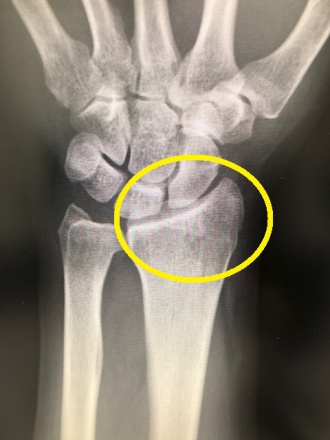

写真は手の関節の検査。

レントゲン画像(右)→ 分かりにくいですね…